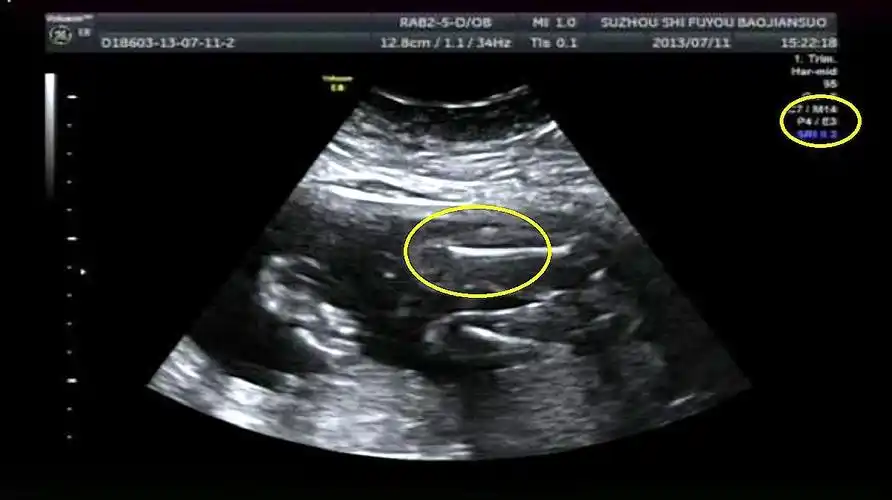

辨别胎儿性别有方法,b超单上一清二楚,再也不用求医生了!

当看到女儿的b超检验结果,她更加不敢相信自己的眼睛——胎儿已经31周